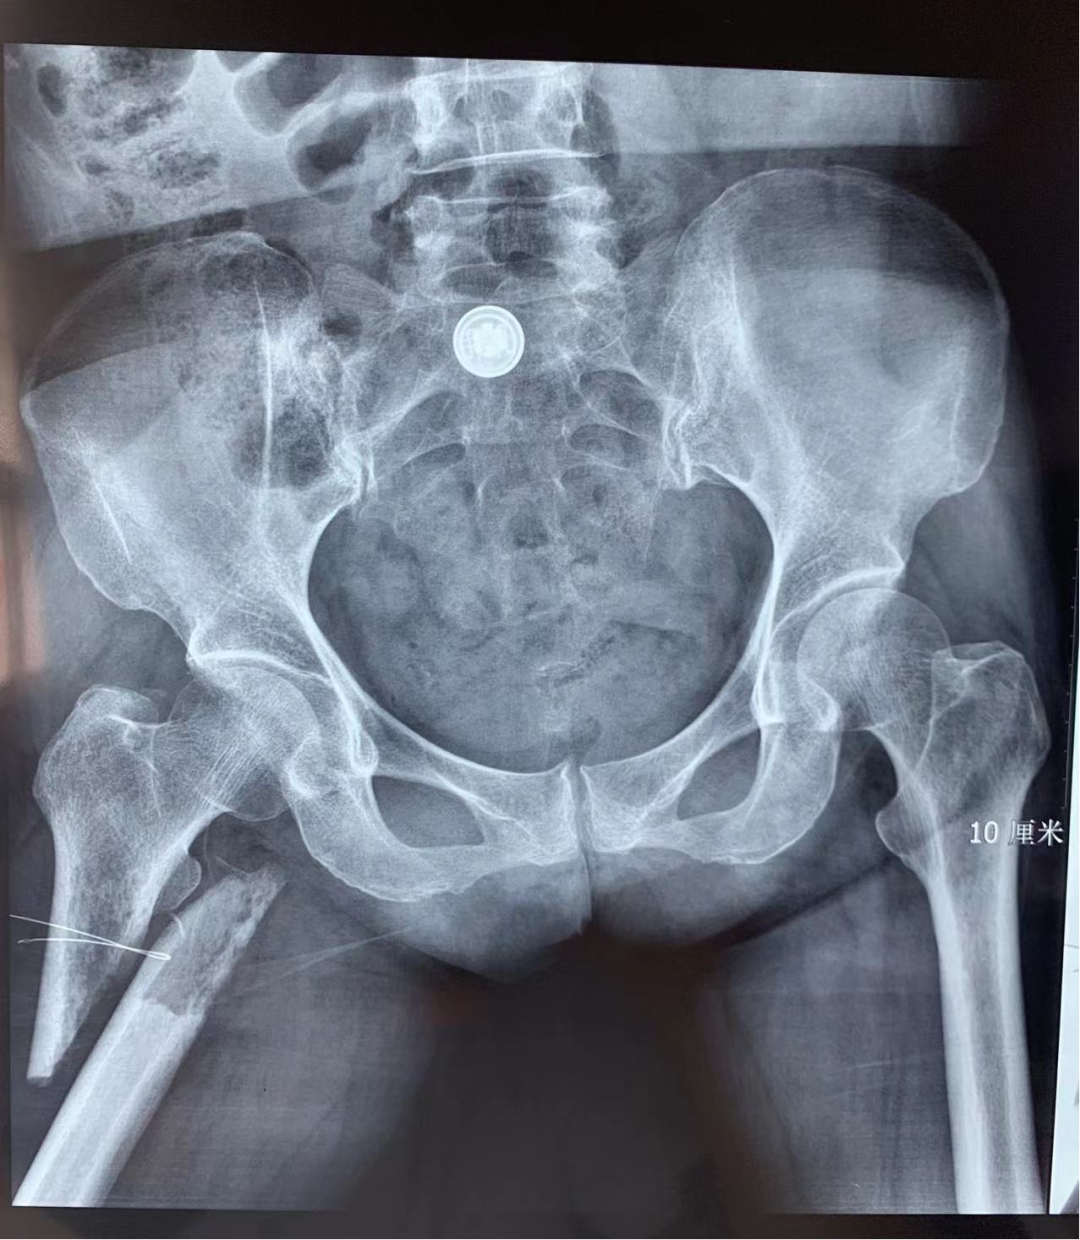

患者为64岁女性,因“右髋部疼痛伴活动受限1天”在当地医院就诊,诊断“右股骨粗隆下病理性骨折”后转至我院就诊,外院CT及MRI检查提示恶性肿瘤全身多发转移,原发肿瘤未明确,患者右髋部疼痛难忍,无法坐立。

▲术前X线